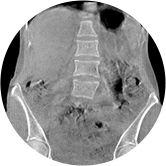

腰椎

關閉金屬偽影校正

開啟金屬偽影校正